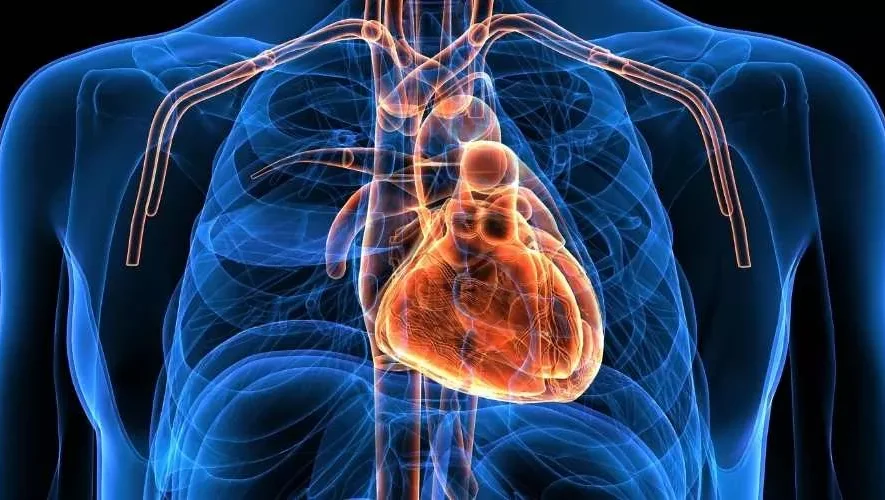

خدمات عيادة القلب في مجمع الرقي الطبي العام – راحة قلبك تبدأ من هنا

تُعد خدمات عيادة القلب في مجمع الرقي الطبي العام بمكة المكرمة وجهة مثالية لكل من يبحث عن رعاية متكاملة لصحة القلب والأوعية الدموية. يجمع هذا القسم بين الخبرة الطبية العالية وأحدث التقنيات التشخيصية والعلاجية لضمان راحة المريض وسلامة قلبه. فكما يقولون، القلب هو المحرك الأساسي للحياة، والعناية به تبدأ من اختيار المكان المناسب الذي يوفر لك رعاية دقيقة وشاملة، وهذا ما يقدمه مجمع الرقي الطبي العام بكل فخر.

رعاية شاملة لصحة القلب

في مجمع الرقي الطبي العام، تهدف عيادة القلب إلى تقديم خدمات طبية متكاملة تشمل الوقاية، التشخيص، والعلاج، تحت إشراف فريق طبي متخصص في أمراض القلب والشرايين. يبدأ الاهتمام بالمريض منذ لحظة دخوله العيادة، حيث تُجرى له فحوصات دقيقة لتقييم صحة القلب مثل تخطيط القلب (ECG)، وفحص الموجات الصوتية للقلب (الإيكو)، إضافة إلى قياس ضغط الدم ومتابعة نسب الكوليسترول والدهون في الدم.